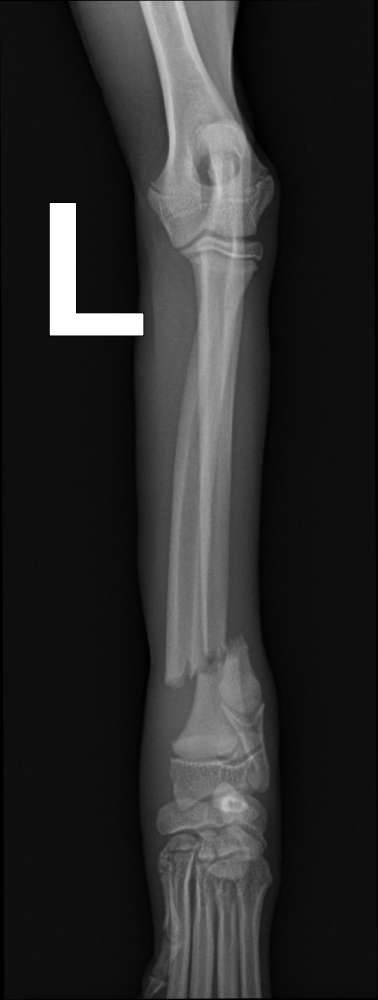

Unsere Aileen hat einen Beinbruch mit 4 Monaten gehabt.

Das ist bei einem normal Gang durch eine Wiese passiert.

Sie trat in ein Loch und da die Knochen so weich waren, ist der Bruch passiert.

Koko hat sich mit 4 Monaten die Elle und Speiche gebrochen da von Stuhllehne gesprungen. Nach 3 OPs und 3 Monaten nerven aufreiben alles wieder gut. Sonst eher robust.

Unsere Aileen auch, da sind die Knochen so weich. Von meiner Freundin der Sheltie auch mit 4 Monaten. Aileen ist nur auf einer Wiese gegangen, noch nicht einmal gelaufen. Dort muss ein Loch gewesen sein. Beide Ellen durch und bekam eine Platte, die andere konnte so heilen. Das Gejammere, weil sie spielen wollte war schlimm. Meine Nerven waren blank. Wir mussten 4 Monate auf Heilung warten. Das schlimme, habe noch 2 Shelties. Die eine war da 14 und der Kopf war nicht mehr so klar. Dass ich keinen Nervenzusammenbruch hatte, das wundert mich. Aileen wird im August 2 Jahre und im Winter macht die Platte keine Probleme. So läuft und springt sie, als wäre nie was gewesen. Wie geht es Kokos Bein ?

Das hatten wir auch mal mit 3 Monaten. Haben 5 OPs hinter uns. Aber das passiert bei jeder andere Rasse